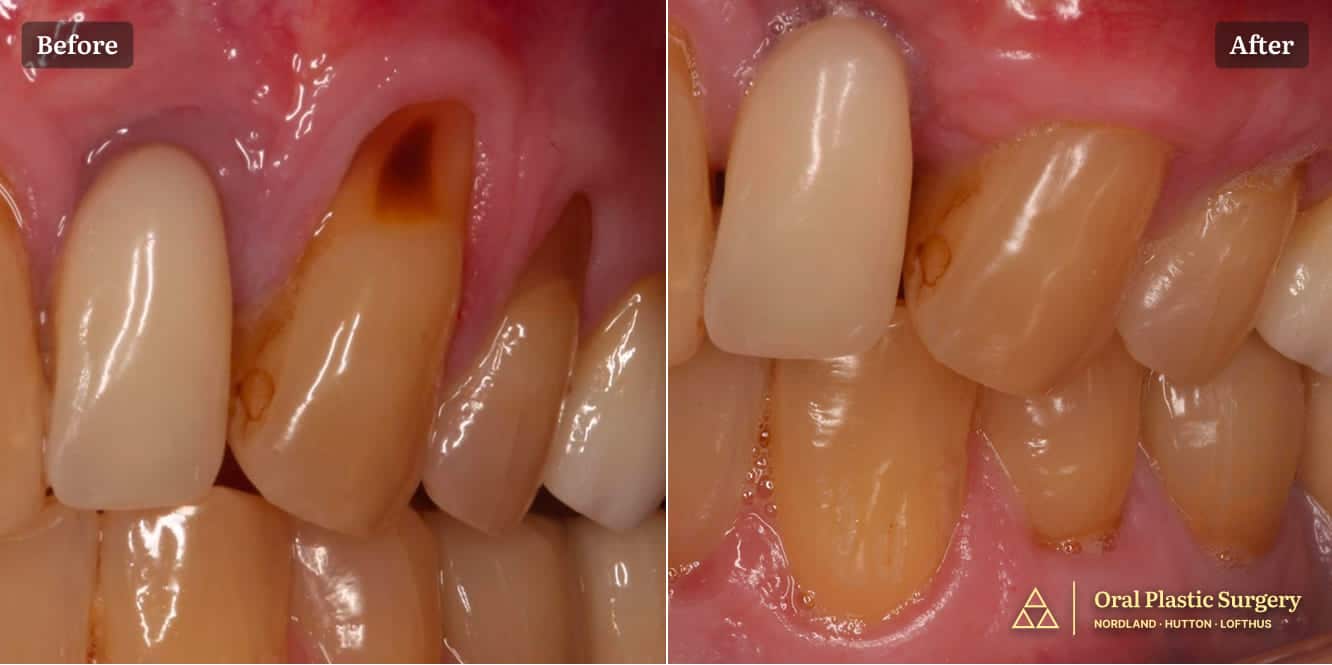

The before image shows recession affecting multiple teeth in the left quadrant, with visible root exposure The after image shows post-operative outcome demonstrating successful root coverage and increased width of keratinized tissue